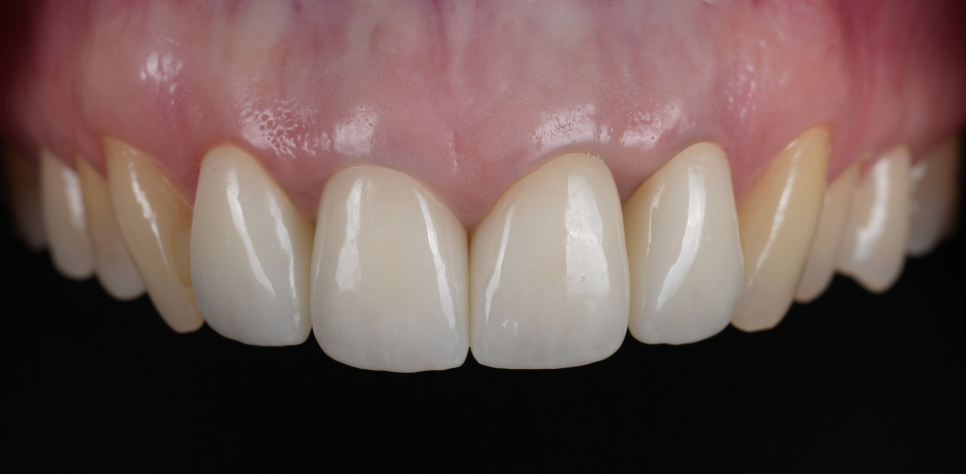

신경치료 후 어두워진 색상이나 신경이 죽은 경우 등 내부 변색이 원인일 때는 실활치 미백을 진행한 뒤 치아 색이 충분히 밝아지면 그다음 단계에서 새로운 크라운을 제작하고 있어요.

이렇게 하면 웃을 때나 얘기를 할 때 보이던 검은 선이 훨씬 자연스럽게 개선되는 경우가 많거든요^^

오래된 접착제가 원인이거나 PFM 보철의 금속 부분이 겉으로 드러나 보이는 경우에는 접착제를 깨끗하게 제거한 뒤 새롭게 제작하거나 금속이 없는 지르코니아 크라운으로 교체를 도와드리고 있어요.

1mm의 디테일이 앞니 크라운의 '한 끗'을 결정합니다.

앞니 치료는 결국 자연스러움과의 싸움입니다. 단순히 새로 덮어 씌우는 기능적 치료를 넘어, 환자분의 미소 속에 녹아들어야 하기 때문이죠.